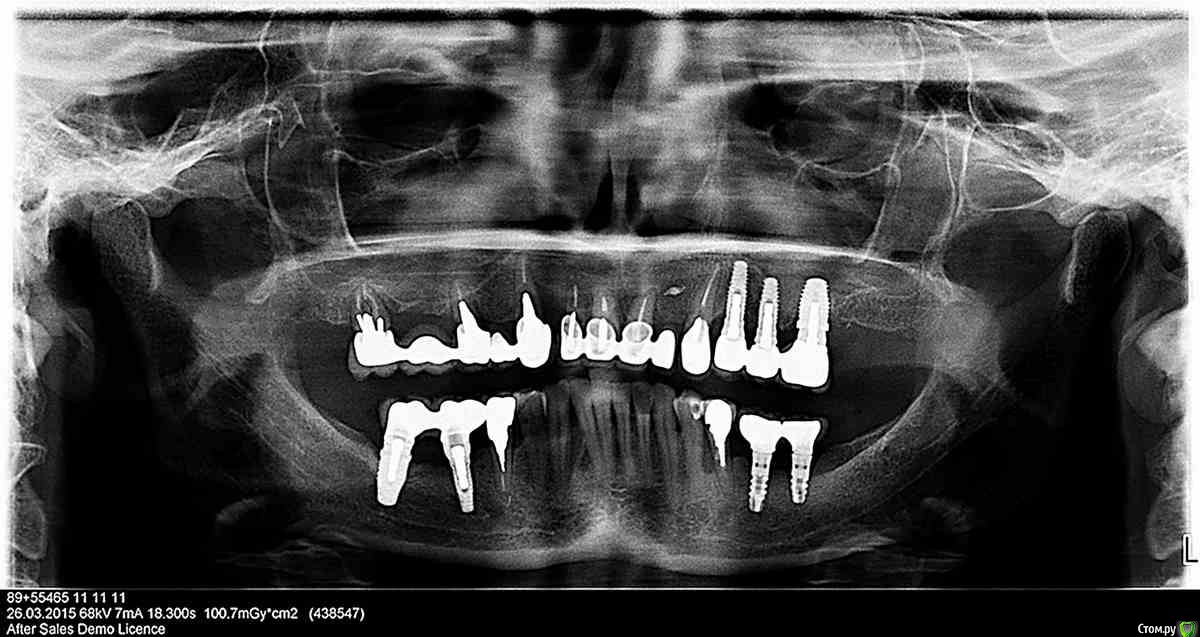

Елена2204 Опубликовано 27 марта, 2015 Поделиться Опубликовано 27 марта, 2015 Здравствуйте! Очень понравился ваш форум. Несколько дней подряд читала интересующие меня темы. Узнала очень много нового, развеяла многие сомнения...Спасибо большое создателям! Но все таки очень хочется услышать мнение о своем конкретном, очень наболевшем, случае.Мне скоро будет 53. Я из Санкт-Петербурга. Лет двадцать назад пережила разбойное нападение с целью отъема сумки. Закончилось вывихом двух передних зубов 21 и 22 (если я правильно определила, как стоматологи нумеруют леве верхние). Ставили в дежурной больнице, куда привезла скорая, железную шину, к которой проволокой за десну закрепили эти зубы на место. Выглядело это варварски, но зубы закрепились, шину со временем сняли и энное количество лет я еще прожила с собственным "фасадом". Дальше начались проблемы...Эти два зуба расшатывались и немного опускались вниз. Лет 7 назад, пришлось расстаться с 22, который совсем расшатался. Носила одиночный пластмассовый протез. Очень неудобно. Мучилась. Решилась ставить мост из четырех передних зубов. Для этого умертвили и обточили 11 и 12. Если не ошибаюсь простояла конструкция лет 5. Сейчас она расцементировалась на 11 и 12 и держится на 21 на "честном слове", иначе не скажешь, потому что сам зуб 21 держится еле-еле. Кроме всего соседний мост по закону подлости, тоже пришел в негодность, та как расцементировался на 13 и 15 и держится исключительно на 17. Пришла на консультацию, где сказали, что надо убирать все от 17 до 23. Ставить съёмный протез , затем ждать месяца 4, пока все заживет.Затем синус-лифтинг в районе 15 и 16. Если все хорошо, савим импланты месяца еще через четыре. Цена вопроса была обозначена в районе 600 тысяч + год со съмным протезом . Ушла я с первой консультации в полнейшем шоке и слезах. Через пару дней решила, что не может быть такого, чтобы в 21 веке, не было других способов, как удалить все зубы, уйти без оных на две недели, затем сделать слепки и еще около недели ждать съемный протез, который еще неизвестно как "приживется" у меня....И решила я походить по разным стоматологиям на консультации. Возможно, я не попала, в нужное место, а возможно так и обстоят дела в стоматологии на сегодняшний день...но, к моему огромному сожалению, я слышала от всех один и тот же вышеизложенный план с вариациями в цене и количестве имплантов. В одном месте еще добавился вариант, что когда придет время ставить импланты, может оказаться впереди очень тонкая кость и надо будет делать еще и костную пластику. И что сказать это по КТ сейчас нельзя, когда там есть еще свои корни...В другом месте сказали, что надо при удалении засыпать в лунки костный материал и тогда к моменту имплантации кости будет достаточно. В третьем месте, сходу предложили имплантацию с нагрузкой от 23 до 14, потом синус-лифтинг в раоне 13 и 15...Но слышав на предыдущих консультациях, что кости мало и проблемы воспалительные, была удивлена таким планом... Хочу услышать мнение здешних специалистов. Извините, если напутала с обозначениями зубов. Никогда с этим не сталкивалась. Не умею делать нарезку с КТ, поэтому специально вчера сделала панорамный снимок, чтобы загрузить здесь. В большом размере не загрузился....Будет ли что видно? Ссылка на комментарий

Doc Опубликовано 28 марта, 2015 Поделиться Опубликовано 28 марта, 2015 Больше всего убила сразу фраза, что надо все удалять, потом 600 тысяч, потом на одной из консультаций добавилась возможная костная пластика на передних зубах, которая напугала больше синуса....но больше всего убивает съемный протез и то, что после удаления сказали по-хорошему ждать 2 недели заживления, потом только снять слепок и еще ждать неделю-две эту челюсть...а потом выяснится, что я ни есть, ни говорить с ней не смогу....а у меня работа с людьми. И, конечно, меня очень волнует профессионализм врача, к которому я в итоге попаду....И еще кажется, что где-нибудь в европе, все таки не выпустят человека из клиники гулять две недели без зубов. Возможно, что кажется....Одного снимка, конечно, недостаточно для постановки полноценного диагноза, нужно видеть уровень мягких тканей, линию улыбки, прикус и много чего еще, но мне кажется, что в Вашем случае без съемного протеза вполне можно и даже нужно обойтись, а временные зубы сделать сразу после удаления, установив имплантаты в позицию 14-12-22, закрыв Вам весь передний отдел, может даже консоль на пятерку удастся сделать. Так что будете ходить без шестерки-семерки, но это терпимо. Жевать этими времянками слишком сильно нельзя будет, скорее всего (зависит от качества кости, длины имплантатов и т.д.), но улыбаться можно будет в любом случае полгода и больше. Одномоментно можно провести синус справа и добавить кости в область клыка и вообще везде, куда потребуется. Через два-три месяца установить имплантаты в области синуса и еще через 4 месяца постоянное протезирование. Но все это так, гадание по снимкам. Окончательное решение может принять только врач-имплантолог с ортопедом после осмотра Вас в кресле. Но направление в целом, думаю, именно такое. 1 Ссылка на комментарий